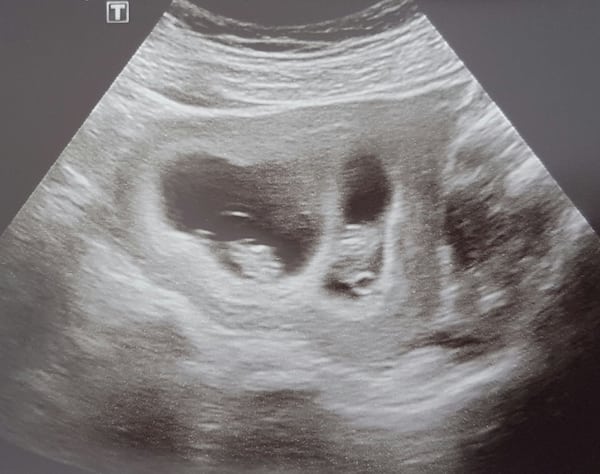

Ultrasound Photos – 8 Week Sonogram

8 week sonogra